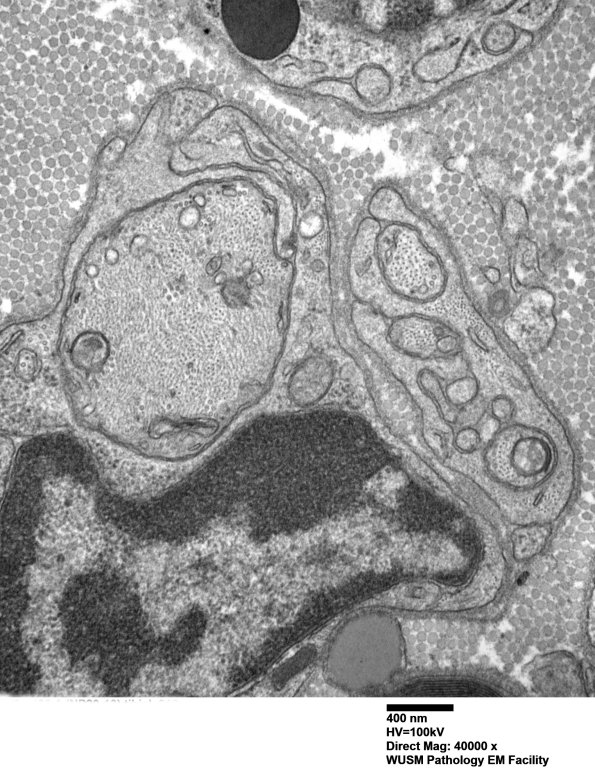

Washington University Experience | PERIPHERAL NEUROPATHY | 1 NORMAL NERVE ANATOMY | 6 Infant Peripheral Nerve | 2B11 W20-132 A (Case 2) tibial_016 - Copy

2B11,12 Pre-myelinated and thinly myelinated axons are numerous in this nerve which is developing rather than degenerating with very little debris. (electron micrograph)